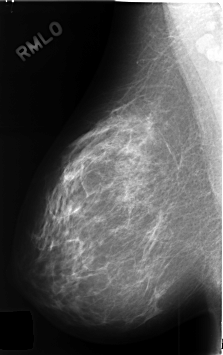

C_0435_1.RIGHT_MLO

RIGHT_CC LINES 4616 PIXELS_PER_LINE 2936 BITS_PER_PIXEL 12 RESOLUTION 50 NON_OVERLAY

RIGHT_MLO LINES 4608 PIXELS_PER_LINE 2888 BITS_PER_PIXEL 12 RESOLUTION 50 NON_OVERLAY